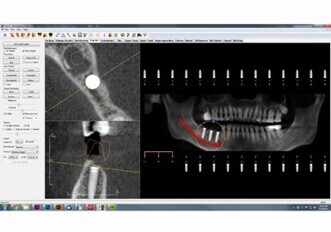

Invivo 5.4

KaVo Kerr Group Imaging is pleased to release Invivo 5.4, an enhancement to the award-winning CBCT 3D imaging treatment-planning software. The new upgrade is fully integrated and exclusively used with...